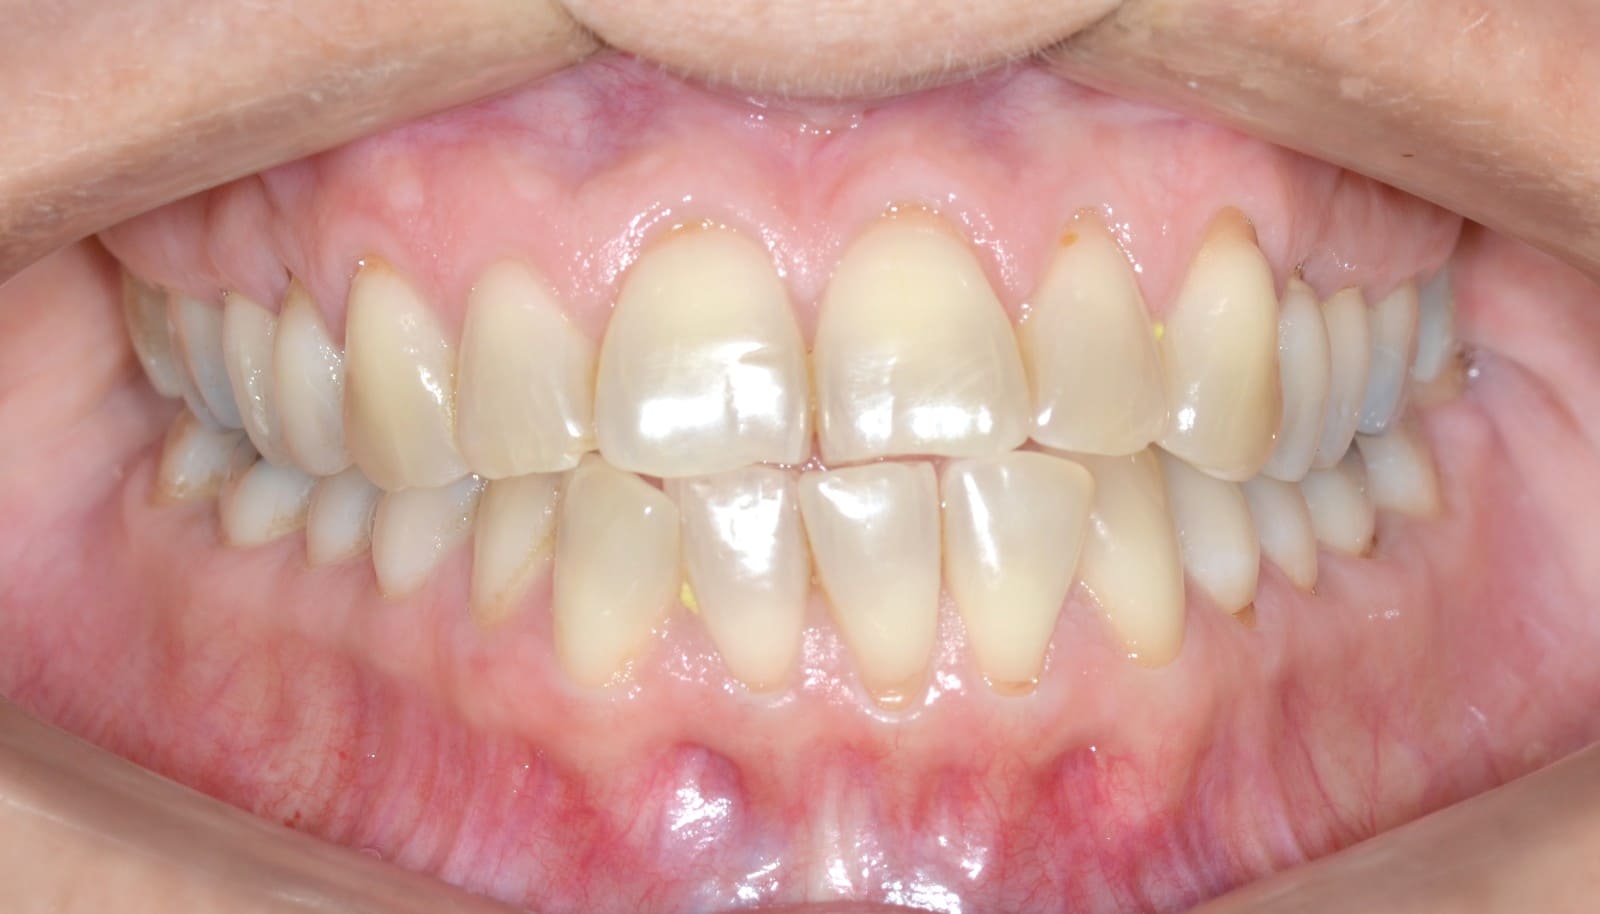

Initial

Final

- Class I relationship achieved

- Functional canine guidance on both sides

- Anterior crossbite corrected

- Normal overjet and overbite achieved

- Midlines coincident

- Proper axial inclination of incisors

- Curve of Spee leveled

- Arches aligned and coordinated

- Arch form improved

- Aesthetic smile line was achieved

- All treatment goals were achieved case